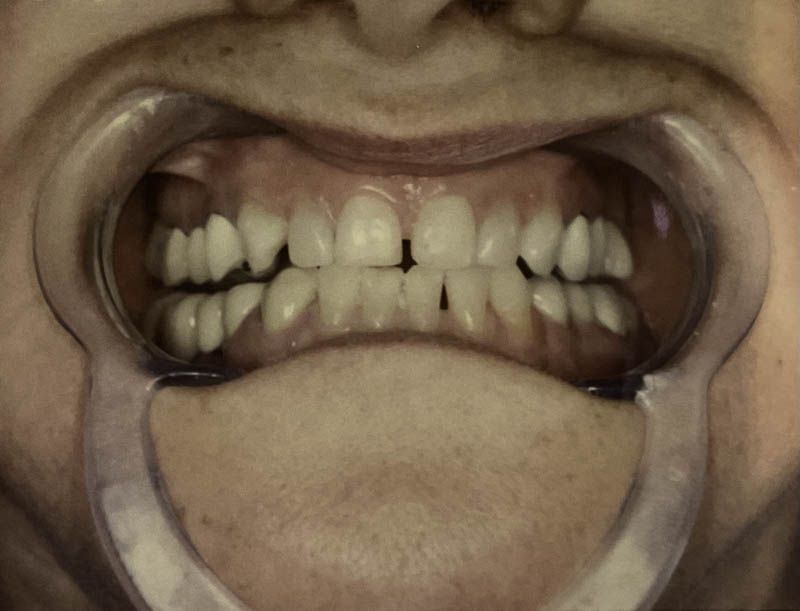

Before

After

Invisalign® Clear Aligners

Case Highlight